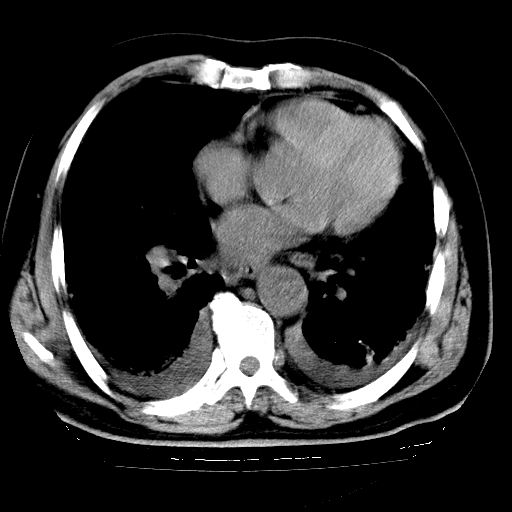

男,68岁,咳嗽、胸闷、发烧三天,查体:双肺散在湿罗音。

首先考虑特发型肺间质纤维化;两侧少量胸腔积液。

依据:1、两肺广泛条索状、网格状、蜂窝状改变。

双肺多发条索状、网格状及小灶状密度增高影。考虑慢支合并感染.间质纤维化,双侧少量胸腔积液

两肺广泛条索状、网格状、蜂窝状改变。肺间质纤维化,肺心病,双侧胸腔积液